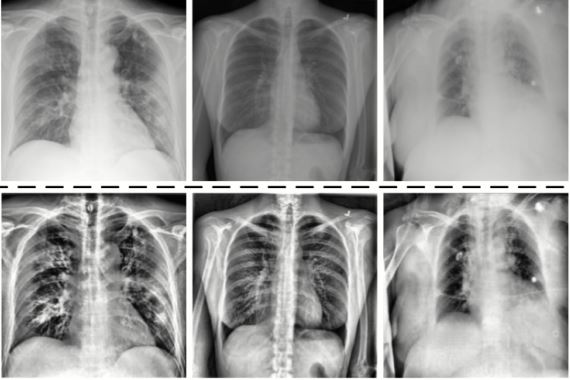

कोरोना भएपछि फोक्सोमा देखिएको खराबी पत्ता लगाउने नयाँ प्रविधिको विकास

१७ माघ, काठमाडौँ । कोरोना भाइरस सङ्क्रमण भइसकेको मानिसको फोक्सोमा हतपत पत्ता नलाग्ने खराबी देखाउने नयाँ प्रविधि पत्ता लागेको छ ।

बेलायतमा यो प्रविधिमार्फत गरिएको प्रारम्भिक अध्ययनले कोभिड भएका मानिसको फोक्सो सहजै पत्ता नलाग्ने गरी क्षति भएको देखाएको अन्तराष्ट्रिय सञ्चारमाध्यमहरुले जनाएको छ ।

नियमित जाँचबाट नदेखिने फोक्सोको अस्वाभाविक रुपबारे अध्ययनका लागि वैज्ञानिकहरूले नयाँ ग्याँस स्क्यान प्रक्रिया अपनाएका थिए ।

कोभिडको प्रारम्भिक चरणमा अस्पतालको उपचार आवश्यक नभएका तर पछि लामो समयसम्म श्वासप्रश्वासको समस्या भएका ११ जनामा यो प्रविधिमार्फत अध्ययन गरिएकोमा नियमित जाँचबाट पत्ता नलाग्ने गरी क्षति भएको देखाएको हो ।

यसबारे अझै बृहत् र विस्तृत अध्ययन भइरहेको खबरमा जनाइएको छ । कोभिड भएपछि अस्पताल भर्ना भएका मानिसहरूमा गरिएको यसअघिकै अध्ययनमा आधारित भएर नयाँ अध्ययन थालिएको थियो ।

अनुसन्धानकर्ताहरूले अध्ययनबाट दीर्घ कोभिड भएका प्रायजसो बिरामीलाई किन श्वासप्रश्वास सम्बन्धी समस्या हुन्छ भन्नेबारे थप प्रष्ट पार्ने बताएका छन् ।

जाँचमा अरू कुनै रोग नदेखिए पनि कोरोना भाइरस सङ्क्रमण लक्षण कयौँ हप्तासम्म निको नहुने अवस्थालाई दीर्घ कोभिड भन्ने गरिएको छ ।